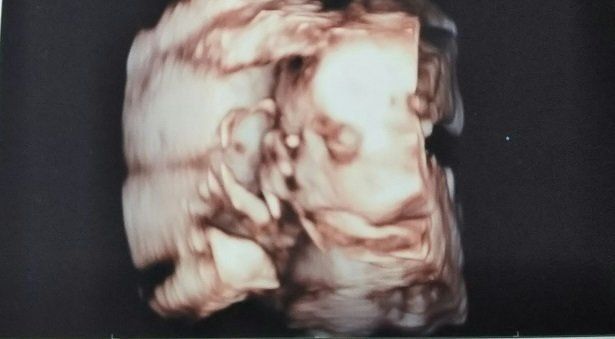

妊娠12週目のエコー写真 赤ちゃんの姿が、だんだんはっきりしてきます

妊娠12週目。赤ちゃんのほうは順調でしたが、私はつわりが強く出てきていました。食べ物の好みもかなり偏り、ソース焼きそばとか、ポテトとか、味の濃いものが食べたいと思うころでした。テレビのCMで食べ物が映るとそればかりが気になっていましたが、いざ食べようと思うと、気持ちが悪くて食べられませんでした。